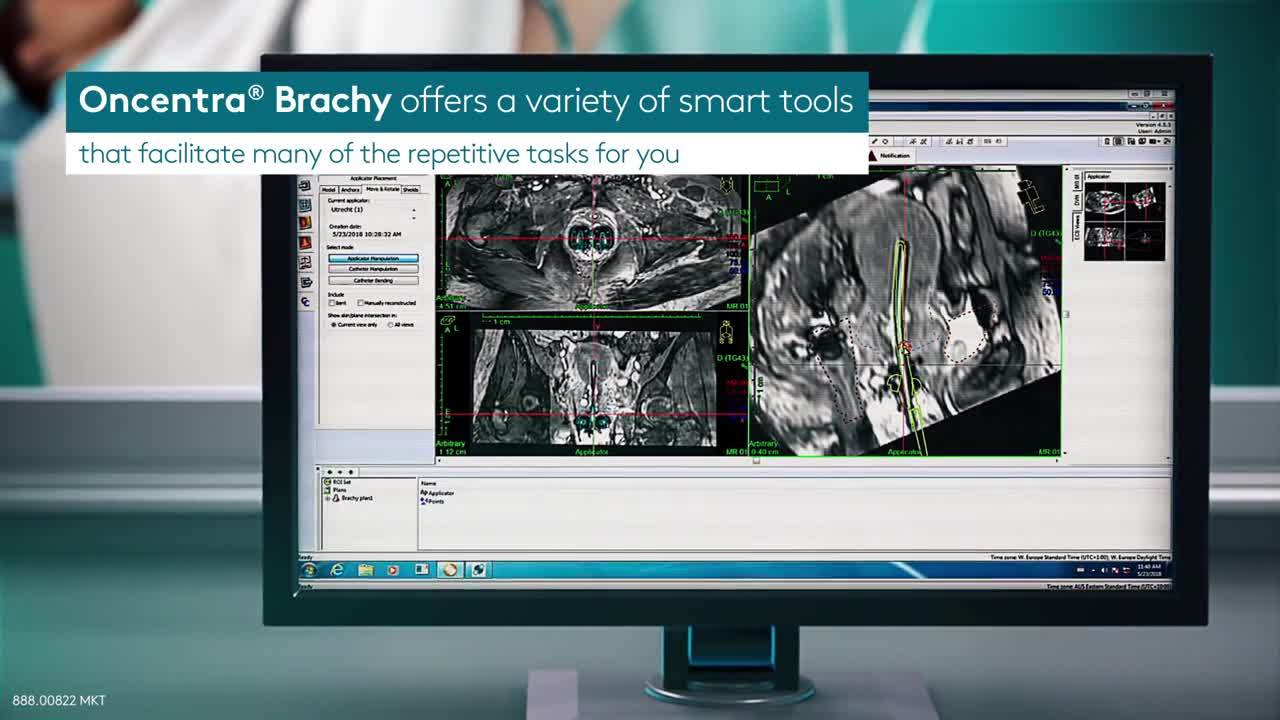

设计最佳剂量分布来治疗肺癌可能是一项耗时的工作。bob体育网赌Oncentra Brachy的最新版本提供了一系列有用的工具,可简化许多重复的任务,例如轮廓和重建。Oncentra Brachy会花时间专注于计数:创建最佳剂量分布。GydF4y2Ba